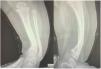

El examen físico reveló la presencia de más de 10 manchas de café con leche de más de 5mm de diámetro. No había efélides. La paciente tenía lesiones amarillentas ligeramente elevadas que medían menos de 1cm en el cuero cabelludo y espalda, así como asimetría de la extremidad inferior izquierda con marcada curvatura (fig. 1). La radiografía simple evidenció engrosamiento cortical y adelgazamiento de la cavidad medular, sugerentes de displasia tibial con pseudoartrosis congénita (fig. 2).

Cabe destacar la rareza del hallazgo de displasia tibial con pseudoartrosis, que solo se encuentra en aproximadamente el 5% de los niños diagnosticados de NF tipo 12. El riesgo de fractura es mayor en este grupo de pacientes2.